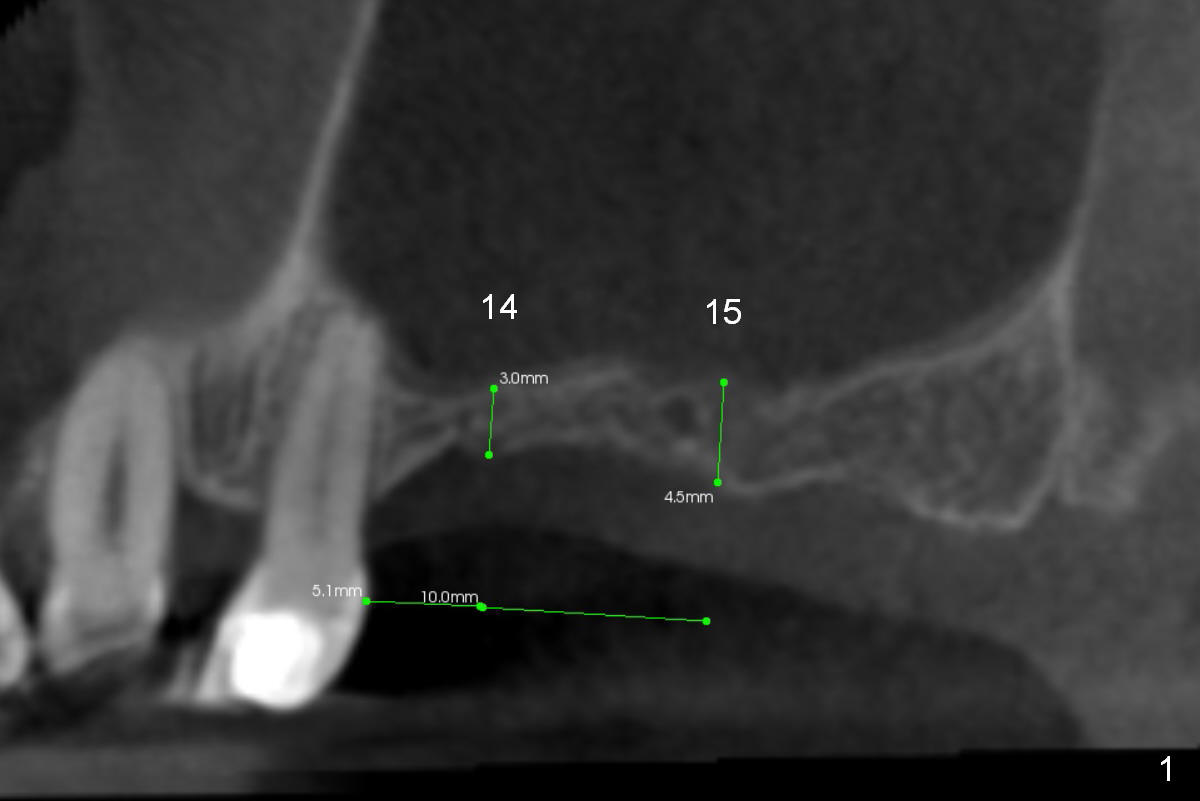

Implants with Sinus Lift in Crestal Approach

A 48-year-old lady has 4 missing teeth: #3, 14, 15 and 31. The sinus floor at #3 is thinner than that at #14 and 15. Sinus lift will be tried on the left side first. Bone height at #14 and 15 is 3 and 4.5 mm, respectively (Fig.1 (CBCT sagittal section). Initial osteotomy depth will be 2 and 4 mm, while final one 4 and 6 mm. The length of UF implants will 8.5 and 10 mm (Fig.2); the diameter will be 5.5 and <5.5 mm (Fig.3,4 (coronal sections)).